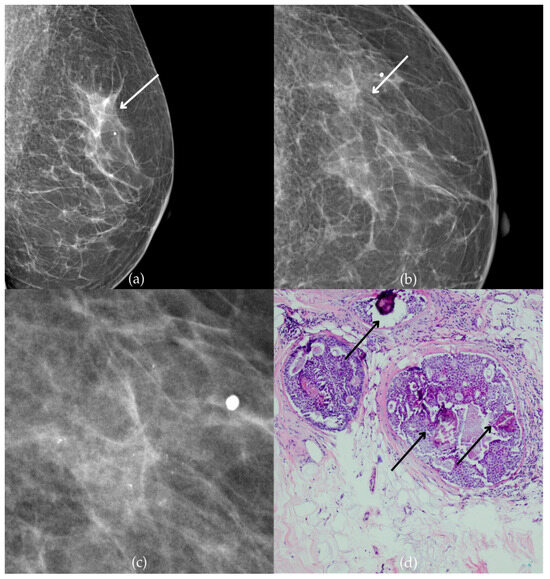

Figure 9 presents mammographic and histopathological images of a 54-year-old patient. The mammogram of the patient’s right breast shows fine pleomorphic calcifications of regional distribution in the upper outer quadrant, corresponding to a BI-RADS 4 finding, due to which a biopsy was performed. Tissue analysis reported ADH and sclerosing adenosis (SA) (category B3). The patient underwent an excisional biopsy (quadrantectomy), and postoperative pathology confirmed the absence of carcinoma. At the most recent follow-up, conducted one year after the initial diagnosis, the US examination was classified as BI-RADS 2, indicating benign findings.

Figure 9.

Atypical ductal hyperplasia (ADH) and sclerosing adenosis (SA). (a) Mediolateral oblique (MLO) view; (b) craniocaudal (CC) view of the right breast showing fine pleomorphic calcifications of regional distribution (marked with arrows) in the upper outer quadrant. (c) Magnified mammographic image of fine pleomorphic calcifications of regional distribution. (d) The histopathological image of the biopsy sample shows ADH (marked with arrows) and SA (marked with arrowhead) (HE staining; 100× magnification).